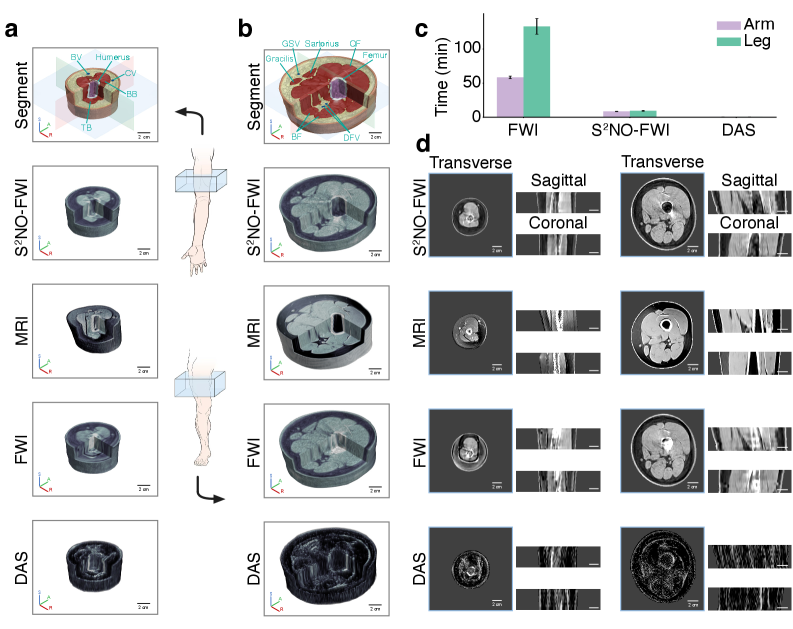

Figure 6a,d and Fig . 7a,c present 3D reconstructions of the arms from both female and male subjects obtained via various methods. The segmented and color‐coded reconstructions demonstrate that the S2NOS^{2}NO‐based inversion effectively restored arm anatomy by the distinct delineation of the skin, humerus, blood vessels (e.g., brachial and cephalic veins), and muscles (e.g., biceps brachii and triceps brachii), while also providing quantitative acoustic maps that reflect muscle stiffness and bone integrity. Moreover, distinct muscle–bone interfaces not only facilitate differentiation between male and female arms based on muscle ratios but also enable the extraction of muscle metrics such as cross-sectional area and volume, which may assist in the diagnosis of sarcopenia (?, ?). Reference MRI images from the same subjects are provided as a gold-standard comparison. Notably, S2NOS^{2}NO outperformed other methods, delivering high-resolution reconstructions with a parameter-free resolution of 1.09 mm, closely approaching the MRI standard of 0.88 mm. Sagittal and coronal cross-sectional reconstructions further demonstrate the consistent performance of S2NOS^{2}NO across different imaging planes. In contrast, the numerical solver, CBS, exhibited scattering artifacts near bone structures and distinct black-ring artifacts in arm reconstructions, indicating that traditional numerical solvers are less robust in strongly scattering samples and tend to overfit to observational noise. In comparison, the S2NOS^{2}NO-based approach demonstrated superior stability.

In Vivo 3D Human Legs

Finally, we applied our method to high-resolution 3D UT imaging of human legs—a challenging yet crucial task for diagnosing sports injuries (e.g., muscle strain, Achilles tendon rupture) and musculoskeletal conditions (e.g., age-related osteoporosis). Using S2NOS^{2}NO-FWI, we achieved high-fidelity 3D reconstructions closely matching reference MRI results (Fig. 6b,d and Fig. 7b,d). For two healthy volunteers (IRB Approval No. IRB00006761-M2024690), we reconstructed 11 mid-thigh slices spanning approximately 5 cm and combined them to yield a 3D sound speed model. Semantic segmentation of the reconstructed volumes (Fig. 6b and Fig. 7b) indicates that S2NOS^{2}NO accurately delineates skin, muscle (e.g., biceps femoris, gracilis, sartorius), fat, blood vessels (e.g., deep femoral vein, great saphenous vein), and femoral structures—including low-density marrow—with a parameter-free resolution of approximately 1.30 mm, an achievement unattainable using classical DAS. The strong scattering in musculoskeletal tissues results in observed signals with extremely low signal-to-noise ratios, complicating the accurate determination of first-arrival times and ultimately causing ToFT to fail in arm and leg imaging applications. Compared to traditional FWI, which required over 133 minutes (around 2.2 hours) for reconstruction per slice, S2NOS^{2}NO completed the imaging under 10 minutes using one NVIDIA A800-80GB GPU. Notably, S2NOS^{2}NO-FWI’s speedup over conventional FWI grows from about 6× for arm imaging to 14× for leg imaging, revealing its superior performance on stronger scattering PDEs. This enables the first successful 3D UT-FWI imaging of human legs, delivering quantitative biomechanical maps that support the diagnosis of conditions rooted in tissue mechanics, such as osteoporosis or muscle degeneration, and underscoring the method’s strong potential for efficient clinical applications where timely diagnosis is critical.

Figure 6: The 3D UT imaging of a female’s leg and arm. (a-b) 3D reconstructions of the female arm (a) and leg (b) were obtained by S2NOS^{2}NO-FWI, MRI, traditional FWI and DAS, and assembled from 11 segmented slices. The color-coded segmentations of S2NOS^{2}NO-FWI reconstruction are shown for both models. S2NOS^{2}NO-FWI outperforms DAS and traditional FWI, delivering high-resolution 3D UT reconstructions with MRI comparable image quality. (c) A comparison of computational times across inversion methods reveals that S2NOS^{2}NO achieves at least a fourteen-fold acceleration. The bars represent the mean ± standard deviation, sample size N=11. (d) Representative transverse, sagittal and coronal sections obtained by S2NOS^{2}NO-FWI, MRI, FWI and DAS demonstrate that S2NOS^{2}NO maintains consistent accuracy across all orientations. BF, biceps femoris; QF, quadriceps femoris; DFV, deep femoral vein; GSV, great saphenous vein; BB, biceps brachii; TB, triceps brachii; BV, brachial vein; CV, cephalic vein.